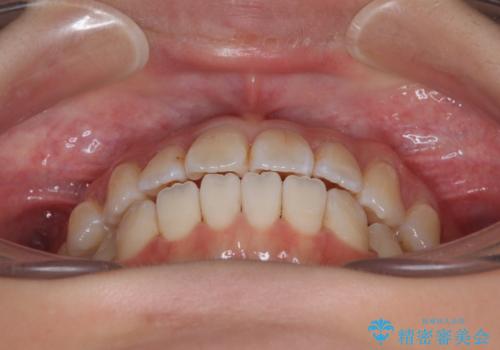

舌の突出癖が原因 インビザライン矯正による開咬改善

- 前歯の開咬を気にして来院された患者様です。

開咬の治療は、前歯を閉じるように動かすとともに、上下臼歯を圧下(骨内にめり込ませる)させることで進めて行きます。

インビザラインは臼歯の圧下を効果的に行えるため、インビザラインを用いて矯正治療を行うこととしました。